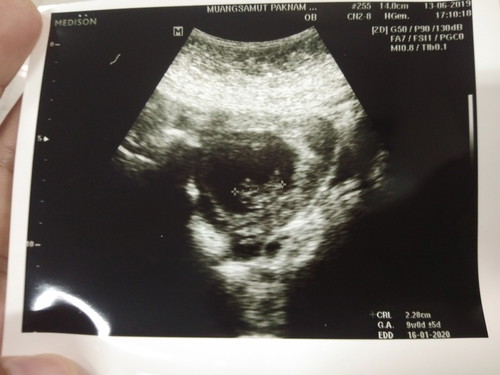

รูปแรกของเบบี้ ? 8สัปดาห์กว่าๆขนาด2.28เซนเล็กไปไหมค่ะขอคำเนอะนำหน่อยค่ะ